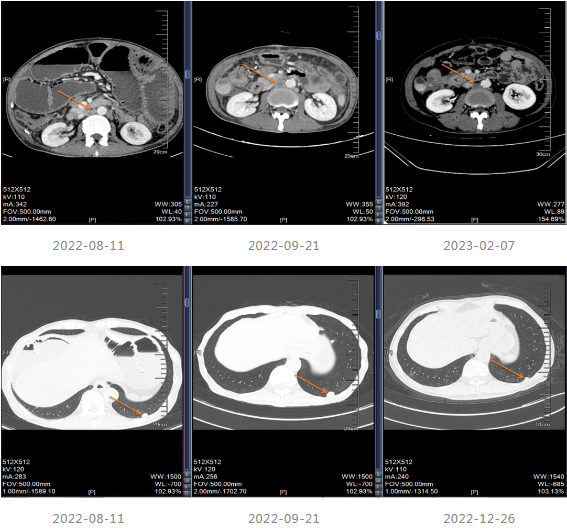

202-08出现肠梗阻,内科治疗效果不佳。

2022-08-29至武汉同济医院行小肠造瘘术。

患者出现肠梗阻,考虑病情PD,因此2022-10-06至今采用“斯鲁利单抗(200mg q3w)+呋喹替尼(4mg/d,口服,服3周停1周)”进行治疗,治疗过程中患者一般情况良好,体重增加。